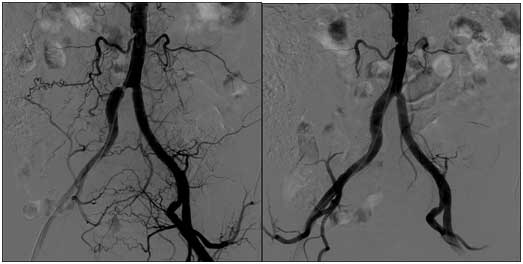

Damar açıcı bitkiler damar tıkanıklığına iyi gelen bitkiler damar tıkanıklığı sorunu genellikle ameliyat ya da anjiyo gibi yöntemlerle tedavi edilebilen ya da bizler tarafından öyle sanılan damar hastalıklarıdır. Damar tıkanıklığına iyi gelen bitkiler damar açıcı doğal formül bitkisel çözüm ahmet maranki. Damar tıkanıklığına iyi gelen şifalı bitkiler hakkında merak ettiklerinizi bu yazıda okuyabilirsiniz alıç meyvesi alıç meyvesinin çiçeği ve yaprakları. Maydanozdan sapları ile beraber 10 12 parça almak yeterli olacaktır.